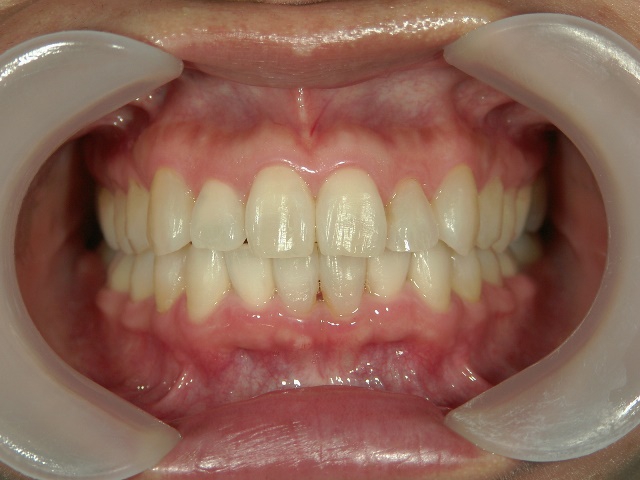

矯正歯科 治療後矯正歯科 プチワイヤー矯正 治療後矯正歯科(プチワイヤー矯正)治療後

プチワイヤー矯正 症例(23

41歳女性 浜松市浜北区在住

治療期間 1年3カ月

主訴:下の前歯の歯並びが乱れていて、舌に当たって痛い。

矯正歯科 治療後 ミニインプラントを2本埋入し、下顎前歯を圧下